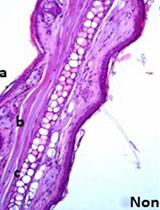

Representative data

Figure 3. Typical survival curve in mice challenged with MHC Class I mAb against H2Kd (1 mg/kg, i.v.) vs. vehicle control